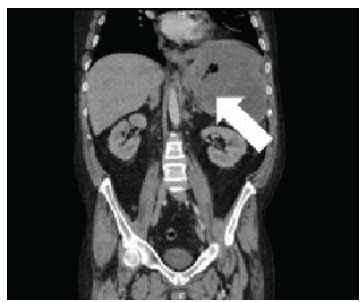

Introduction: A gastrosplenic fistula (GSF) is a pathologic connection between the spleen and stomach that can lead to life-threatening complications. A GSF can arise spontaneously but is often secondary to a variety of etiologies. Most commonly, GSFs arise from gastric or splenic non-Hodgkin diffuse large B-cell lymphomas (DLBCL). Only 46 cases of GSFs have been published to date, and due to its rarity extensive literature review is insufficient for characterization of GSFs.

Case report: This case discusses a patient with intermittent abdominal pain and weight loss, which led to the diagnosis and treatment of a GSF and DLBCL. The patient later went into remission for his DLBCL but succumbed to respiratory failure from a secondary abdominal-pleural fistula formation. Gastrosplenic fistulas have the potential to cause fatal, massive, upper gastrointestinal hemorrhages, infections, other fistulas, or esophageal obstructions. A delay in diagnosis corresponds with a higher morbidity and mortality; thus, prompt detection and treatment are imperative. The management of GSFs is complex and requires a multidisciplinary approach to care.